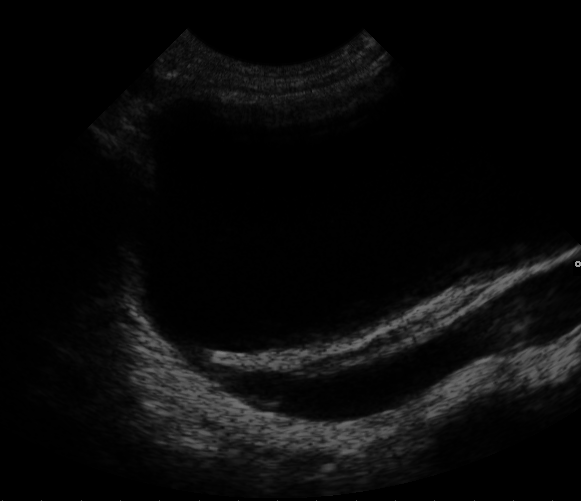

Congenital Horseshoe Kidney

Congenital Horseshoe Kidney. Axial CT image of the abdomen showing a horseshoe kidney. Hellerhoff. Not altered. CC BY-SA 3.0